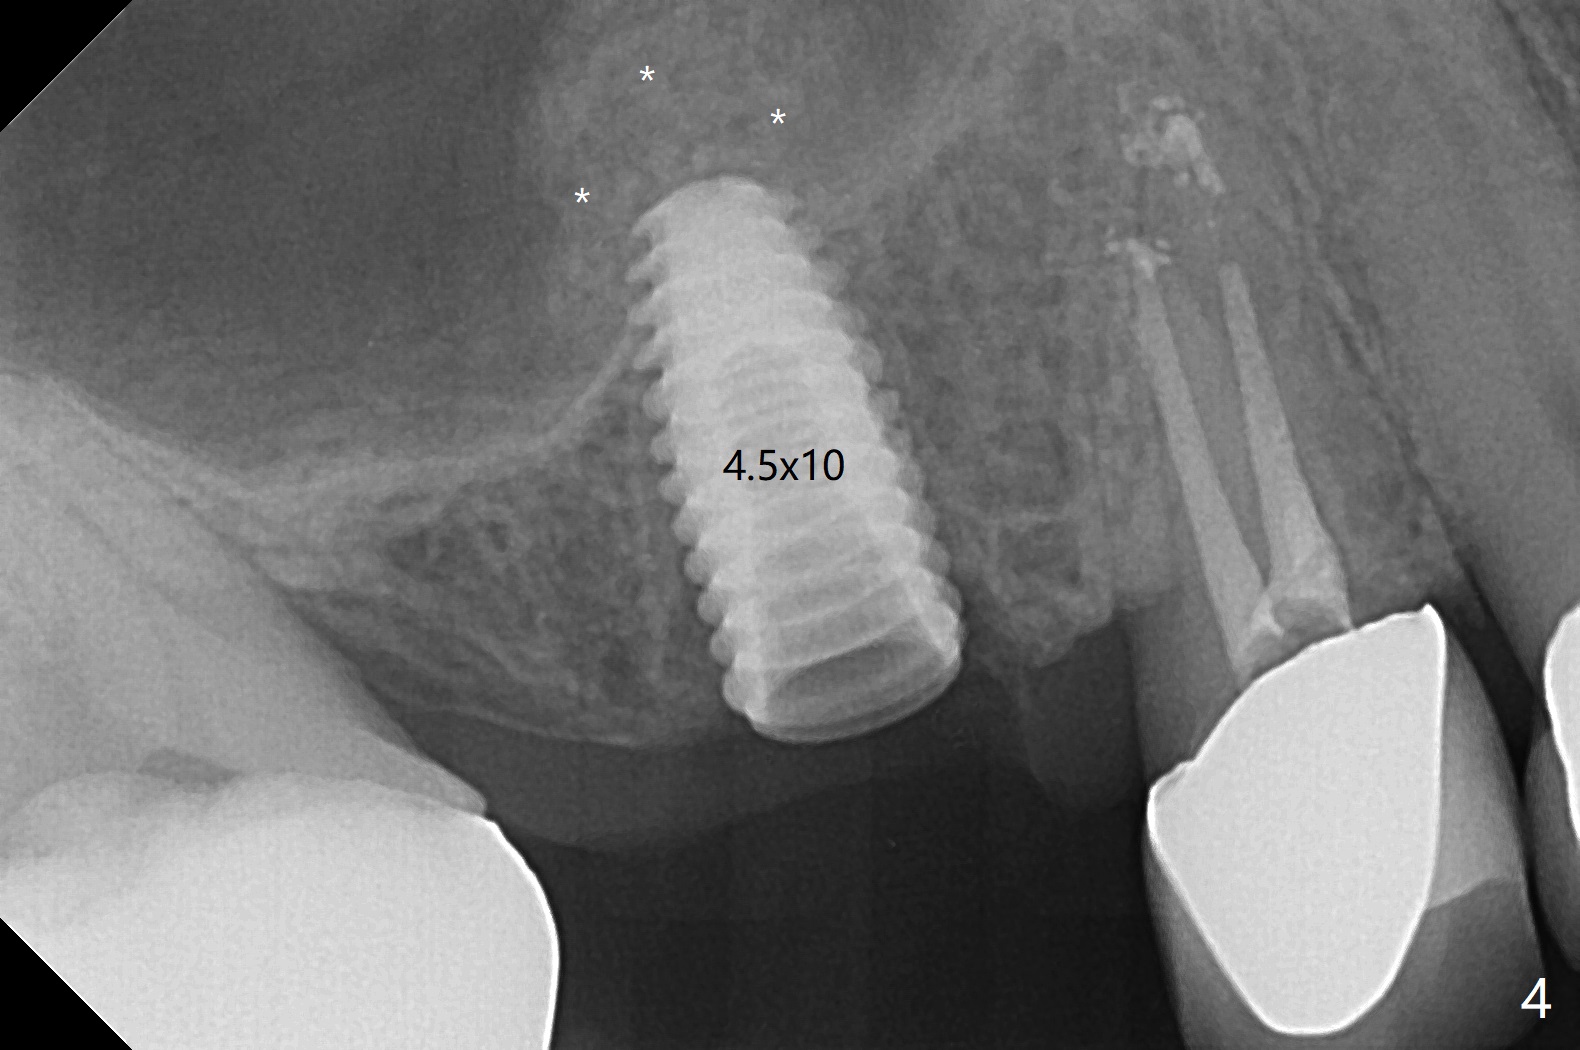

After flattening the root stump with surgical burs and bone trimmer at #4 (Fig.1), it is difficult to use point drill and 2.2x7.3 mm drill because of incomplete engagement of drill cylinder with guide sleeve (Fig.2). The initial osteotomy seems to be buccal. With removal of the remaining root, it is much easier to finish osteotomy (better engagement of drill cylinder with the sleeve) and sinus lift with dummy implants (Fig.3,4 (*: bone graft)). Finally a 4.5x10 mm implant is placed (basically in the middle of the socket with even buccal and palatal gaps) with primary stability and a cemented abutment is hand tightened (after 5.5 mm profile drill) for an immediate provisional (Fig.5). The gingiva is healthy around the provisional with almost perfect seal 2 weeks postop (Fig.6 P). There is no obvious bone loss 7 months postop (Fig.7). There is apparent mature bone in the sinus 9 months postop (Fig.8 *).